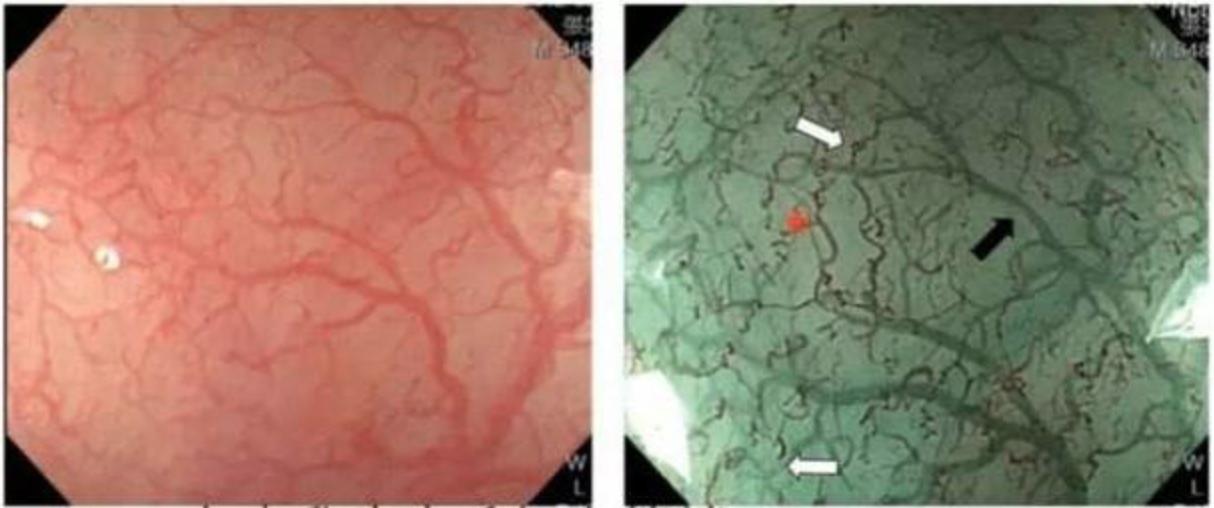

在激光胃镜下如果将有病变的地方继续放大就会得到下列这种图片。

病变区域的血管扭曲的比较厉害

普通白光胃镜主要看病变边界,切换成激光放大胃镜后就可以对病变放大观察,通过判断肿瘤表面的血管的形态、扩张扭曲程度来大致评估肿瘤侵犯的深度以及是否有转移。放大胃镜还可以协助胃镜医生精确的定点夹取病理。